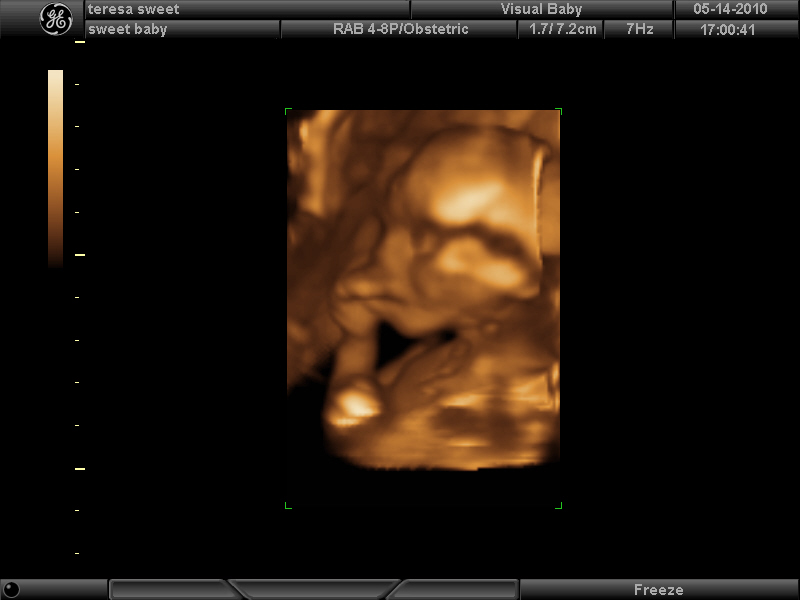

Here’s a few photos in 3D. I’m 17 wks now.

awwwww another boy yay! what a cute name for him, too 🙂 congratulations! how exciting. the 3d ultrasounds are amazing huh?! i noticed in one pic he had his hand under his chin. lol jacob was sleeping during an ultrasound also w his fist under his chin too and then the next day i woke up and realized that’s how i sleep 🙂 aw he sleeps like his mommy! i will be catching up with you soon (i hope!) lol once he decides to make his debut so you can take his pix. in the mean time we are certainly enjoying our maternity pix-thank you again xo